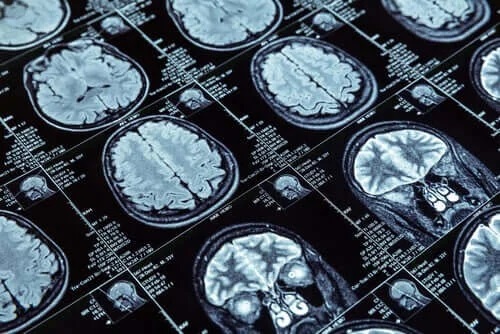

Pentru a efectua studiul, medicii au făcut rezonanțe magnetice nucleare unui număr mai mare de 600 de persoane care aveau 45 de ani în momentul testării imagistice. Aceste 600 de persoane fac parte dintr-un grup mai mare cuprinzând peste 1000 de oameni. Cercetătorii i-au studiat încă din copilărie. Intenția lor a fost să determine factorii care pot influența o persoană de-a lungul vieții și să o facă antisocială sau dependentă. Dacă acești factori pot fi detectați, atunci ar fi posibil să influențăm comportamentul într-un mod pozitiv și să prevenim infracțiunile, de exemplu.

Cercetătorii au măsurat grosimea cortexului cerebral si cantitatea de substanță cenușie prin rezonanță magnetică. Aceste date au permis o comparație între cei care au prezentat un comportament antisocial și cei care nu.

Cercetătorii au descoperit lucruri semnificative despre primul grup. RMN-urile cerebrale ale acestor persoane au arătat o scădere a grosimii cortexului cerebral. În plus, exista o cantitate ceva mai mică de substanță cenușie.

Ceea ce este evident este schimbarea arhitecturii creierului pe care o mică parte a populației o poate avea, cel mai probabil în raport cu tipurile de comportament antisocial. Aceste schimbări ar putea explica personalitatea antisocială care se manifestă persistent de-a lungul anilor.